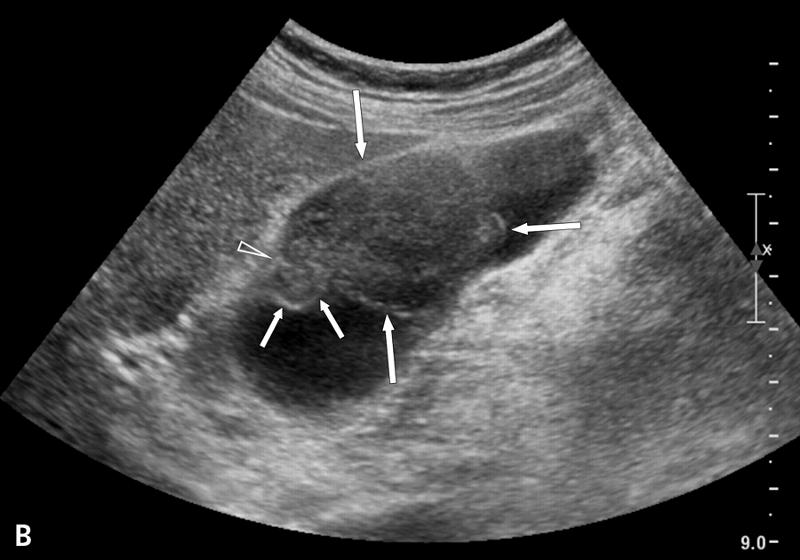

Courvoisier's GB

Distension without wall thickening

due to obstruction distal to the cystic duct

*Panncreatic head mass

* Duodenal papilla mass

*CBD mass